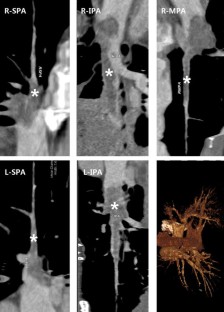

Fig. 1